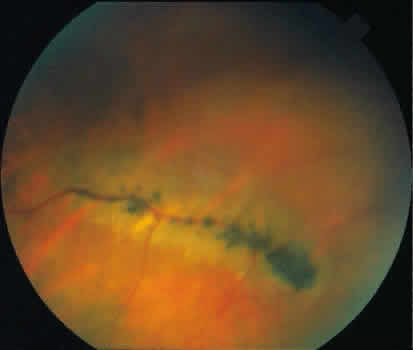

retinal layer; it rarely requires treatment.  Fig. 19. Clinical appearance of typical degenerative retinoschisis: diagram of involved

area and ocular fundus photographs showing optic disc, macula, and

posterior portion of schisis. Within the schisis and adjacent to

the margin is coarse stippling related to broken retinal pillars. Fig. 19. Clinical appearance of typical degenerative retinoschisis: diagram of involved

area and ocular fundus photographs showing optic disc, macula, and

posterior portion of schisis. Within the schisis and adjacent to

the margin is coarse stippling related to broken retinal pillars.